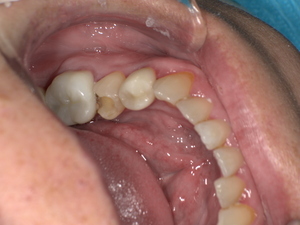

Before:白い詰め物がとれて、見た目も清潔感に欠ける状態。

After: セラミックで修復され、天然歯のように自然な白さと透明感がある美しい歯の状態。どこが治療箇所か分からないほど自然な白さへ。